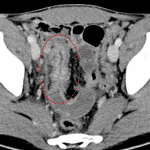

Indication: Right lower quadrant pain

- Marked bowel wall thickening and mucosal hyperenhancement of the terminal ileum with surrounding fat stranding and adjacent peritoneal thickening

- Distal appendiceal wall thickening and dilation with periappendiceal stranding and a possible small fistulous connection between the appendix and the terminal ileum

- Small amount of free fluid in the right paracolic gutter and layering in the anatomic pelvis

- Multiple mildly enlarged ileocolic lymph nodes, likely reactive

- Crohn disease

Marked inflammation of the terminal ileum consistent with infectious or inflammatory ileitis. Crohn disease is a primary consideration given location.

Distal appendiceal inflammation and possible fistula between the appendix and terminal ileum which may relate to acute appendicitis or appendiceal involvement of Crohn disease.